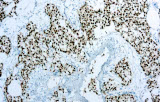

La inmunohistoquímica (IHQ) se ha convertido en un componente esencial de la patología genitourinaria (GU) moderna, permitiendo la caracterización precisa de tumores que afectan a la próstata, riñón, vejiga urinaria y testículo. La literatura revisada por pares destaca consistentemente que la morfología sola puede ser insuficiente en biopsias difíciles o muestras de tejido limitadas; por lo tanto, los paneles de IHQ basados en anticuerpos desempeñan un papel central en el diagnóstico diferencial, la clasificación tumoral y la toma de decisiones clínicas guiadas por biomarcadores.

Alta especificidad y sensibilidad diagnóstica

Los datos revisados por pares demuestran que los marcadores de anticuerpos seleccionados proporcionan una fuerte discriminación diagnóstica, mejorando la precisión en casos difíciles donde la histología rutinaria sola puede ser inconclusa.